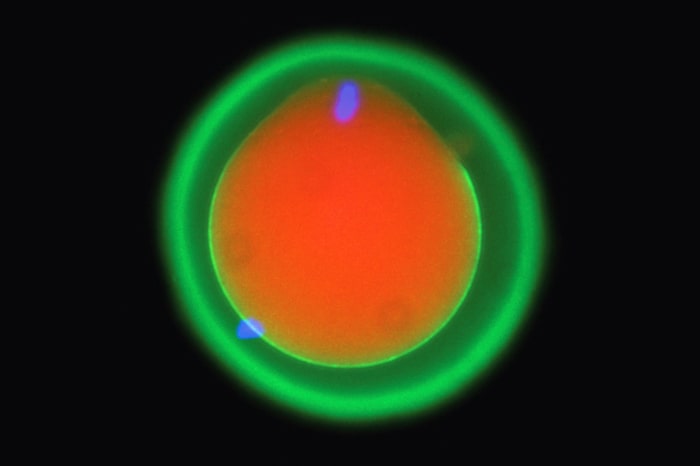

Het team ontdekte dat drie eiwitten op het sperma samenkomen en een soort sleutel vormen die het ei ontgrendelt, waardoor het sperma zich kan hechten. Hun bevindingen, ontleend aan studies bij zebravissen, muizen en menselijke cellen, laten zien hoe dit proces miljoenen jaren van evolutie heeft volgehouden. De resultaten werden donderdag gepubliceerd in het tijdschrift Cell.

Wetenschappers waren eerder op de hoogte van twee eiwitten, één op het oppervlak van het sperma en één op het membraan van het ei. In samenwerking met internationale medewerkers gebruikte het laboratorium van Pauli de kunstmatige-intelligentietool AlphaFold van Google DeepMind – waarvan de ontwikkelaars eerder deze maand een Nobelprijs ontvingen – om hen te helpen een nieuw eiwit te identificeren dat de eerste moleculaire verbinding tussen sperma en eicel mogelijk maakt. Ze lieten ook zien hoe het functioneert in levende wezens.

Het was niet eerder bekend hoe de eiwitten “als een team samenwerkten om ervoor te zorgen dat sperma en eicel elkaar konden herkennen”, zei Pauli.